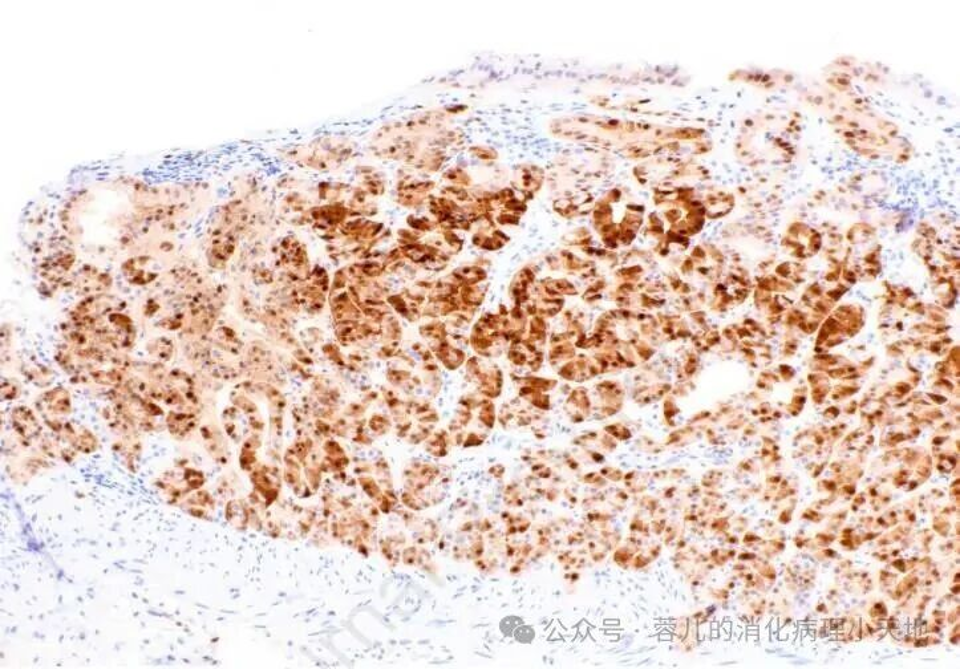

组织学+免疫表型:由黏膜表层下成角腺体组成,表现为主细胞分化、壁细胞分化或两者兼有;表达MUC6但不表达MUC5AC,Cyclin D1弥漫阳性,可作为疑难病例确诊依据

胃泌酸腺腺瘤由扩张且呈角状的腺体组成,这些腺体以主细胞分化为特征,其特征为嗜碱性胞质和均匀的圆形核

Cyclin D1 呈弥漫阳性染色